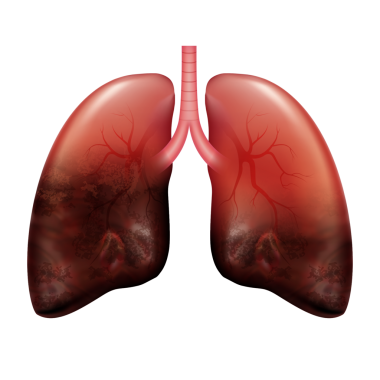

Sağlıklı Bir İnsan Akciğerinin Anatomisi, El Çizimi Suluboya Çizimi

Nefes alsuluboyaOksijenuçak yolculuğuHavalandırmaApexsolunumnefes borusubronşalveollersolunum yolukarbon dioksitSolunum SistemiAnatomik yapısıinsan akciğerMedikal illüstrasyonbronchiolesakciğer fonksiyonbasit örnekthoracic cavityrespiratory healthGaz değişimiVital kapasitehealthy lungmiddle lobetidal volumenormal lungüst lobalt lobbiyolojik diyagramBenzer İçerikler